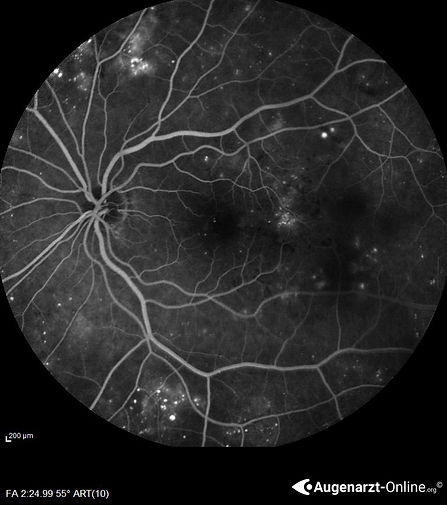

Falschfarbenaufnahme des Augenhintergrunds bei Proliferative Diabetische Retinopathie.